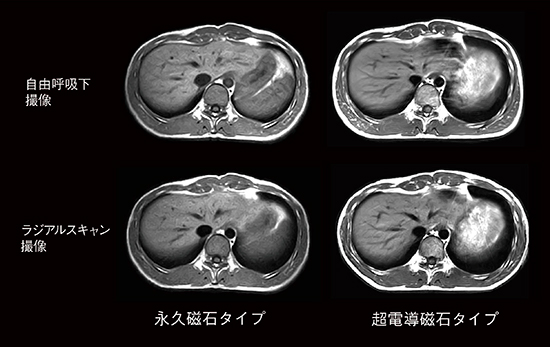

4.動きの影響の強い撮像(図4)

腹部や骨盤腔は呼吸や蠕動運動の影響を強く受けるため,超電導磁石タイプでは呼吸同期や息止め,プリサチレーション,位相方向の変更,運動抑制剤の投与,さらにはラジアルスキャン法などを用いてアーチファクトを抑えて撮像します。永久磁石タイプでは,撮像時間や撮像枚数,脂肪抑制などで不利な面がありますが,同期なしの安定呼吸下でアーチファクトを少なく撮像できるメリットもあります。

図4 腹部画像の違い